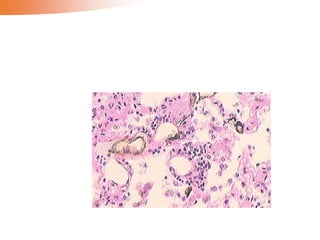

Microscopically, the nutmeg pattern results from congestion around

the central veins, as seen here. This is usually due to a "right sided" heart failure.

• Microscopic changes in ‘nutmeg’ liver:

1) Atrophy and/or necrosis of the liver cells in the

mainly in centrilobular regions

2) Fatty change of the liver cells in the peripheral

part of the lobules